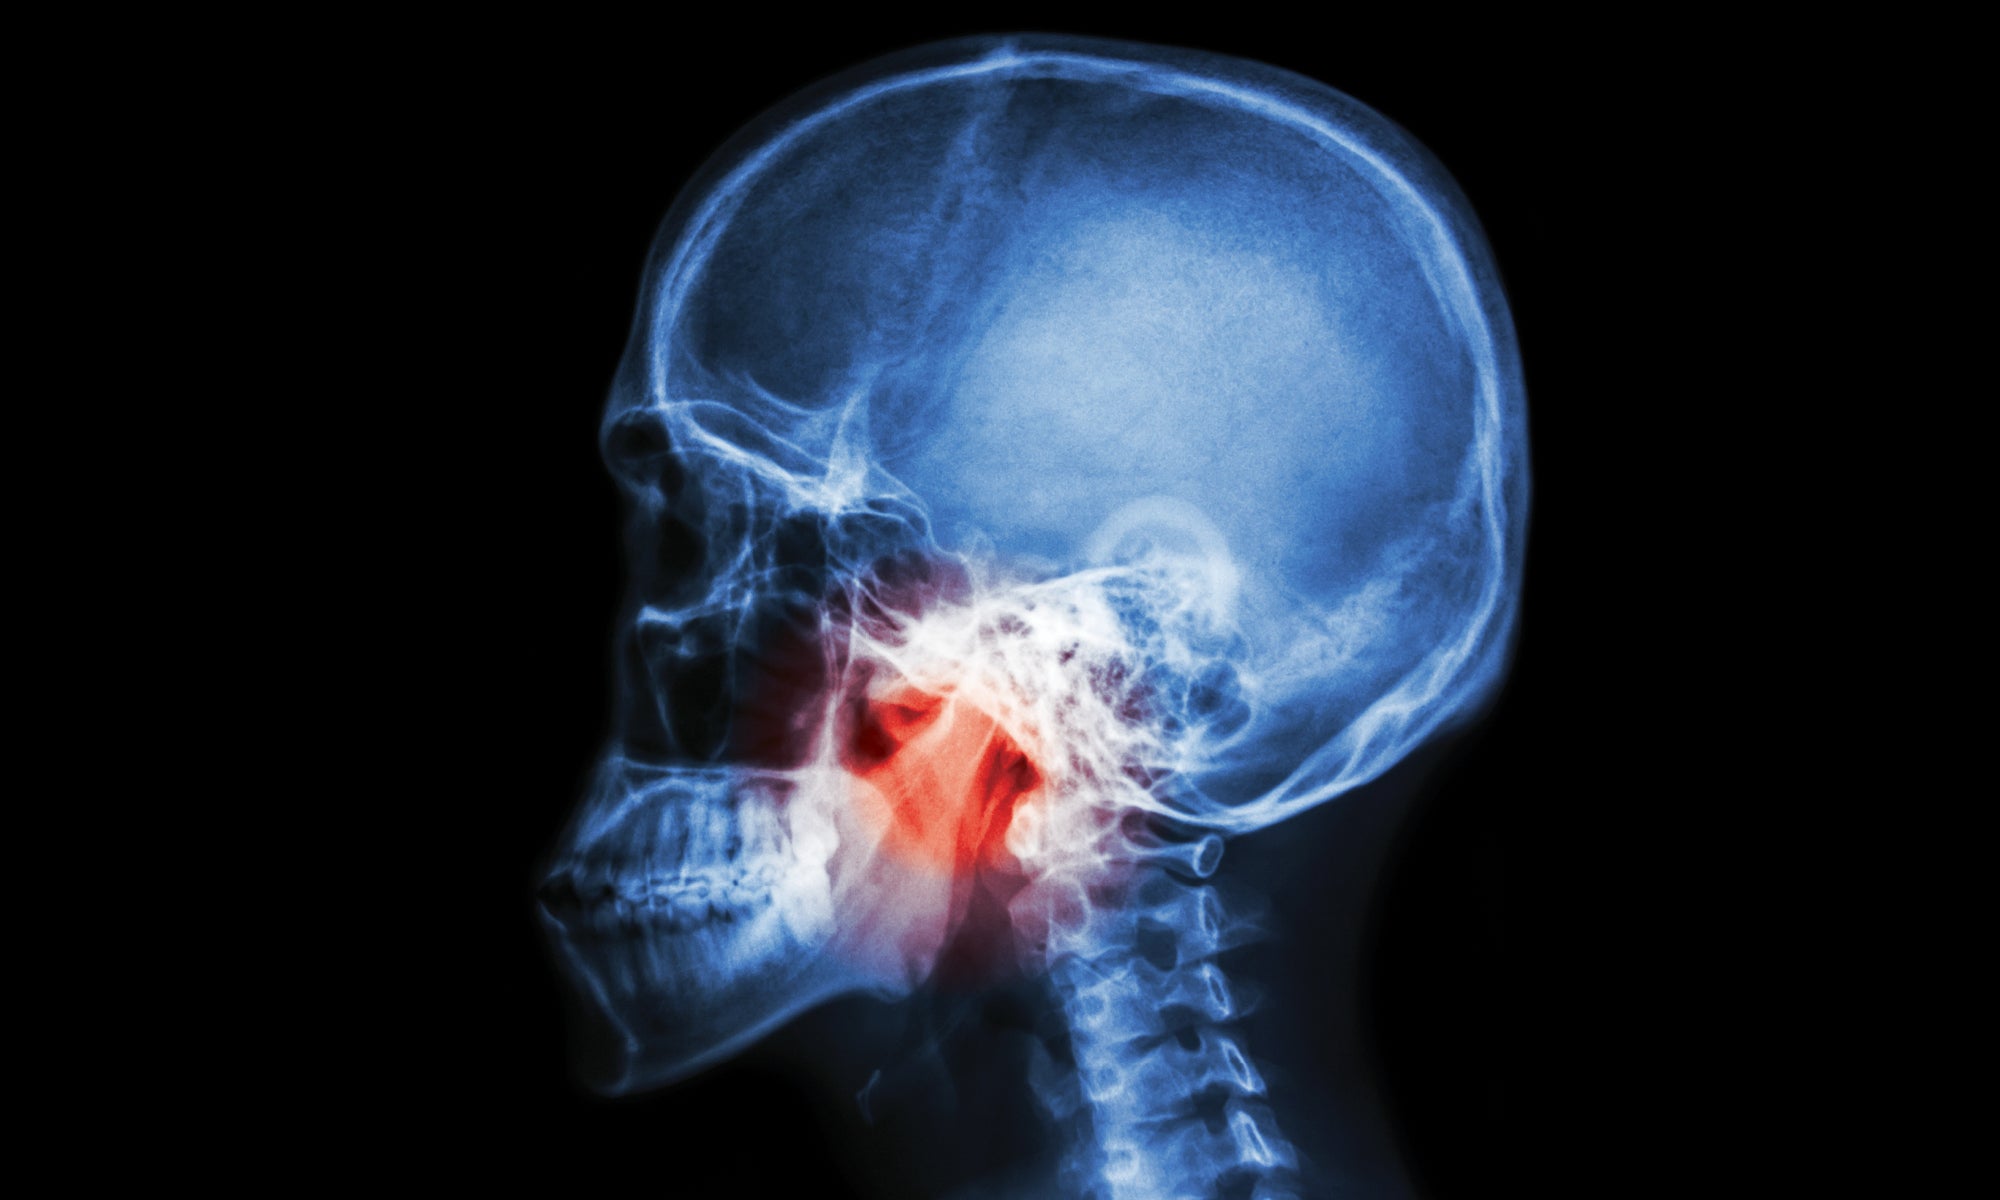

With training in the latest endoscopic and mimimally invasive technologies, the expertise that Jason Ohlstein, MD, brings to LVPG Ear, Nose and Throat–Pocono means that people who require complex head and neck care won’t have to leave the Pocono region to get it.

Board-certified in otolaryngology and head and neck surgery, Dr. Ohlstein joined Lehigh Valley Hospital (LVH)–Pocono earlier this year. “Previously, some of the more challenging or complex head and neck surgeries had to be sent out of network or out of the area, but now we’re able to offer complex and comprehensive ENT/otolaryngic care in the Pocono region, from pediatrics to older adults,” he says.

That includes head and neck cancers, tongue cancers, tonsil cancers, laryngeal cancers, endocrine surgery, thyroidectomy, parathyroid surgery, salivary gland surgery, advanced sinus surgery for nasal polyps and allergies, and surgical treatment for sleep apnea with the Inspire device.